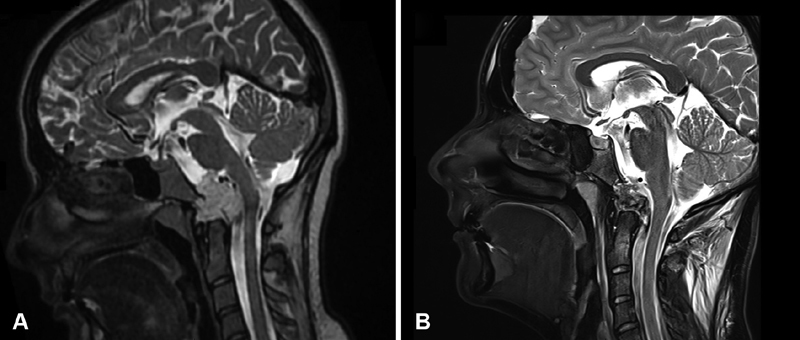

图1,术前和术后磁共振成像(MRI)。(A)术前矢状面t2加权MRI显示以颅颈交界区为中心的高信号病变(脊索瘤),伴有硬膜内延伸和神经血管结构受压。(B)术后矢状T2加权MRI显示肿瘤实现了全切。

术后MRI证实了在没有并发症的情况下实现了全切